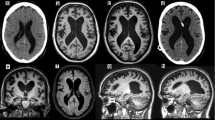

The Evans index (EI) is the most commonly used measure for ventricular enlargement, first described in 1942. It is calculated by taking the ratio of the widest width of the frontal horns of the lateral ventricles and the widest width of the intracranial compartment on an axial image (Fig. 38.1) [38]. International guidelines propose an EI of greater than 0.3 is suggestive of iNPH , although its specificity is questioned [39, 40]. Yamada et al. developed the “z-Evans index” with additional measurements of the frontal horns of the lateral ventricle, resulting in higher accuracy in predicting patient response to a tap test [41].

The callosal angle (CA) is defined by two lines tangentially aligned with the medial walls of the lateral ventricular walls on coronal images. iNPH patients commonly have a CA that is less than 90 degrees, and this has been found to be a good predictor of shunt response [42,43,44]. When combined with an EI of greater than 0.3, iNPH can be discriminated from AD with a sensitivity and specificity of 97% and 94%, respectively [45].

The MR sign described as “disproportionately enlarged subarachnoid space hydrocephalus” (DESH) is characterized by narrowed sulci in the midline at the high convexity, combined with enlarged Sylvian fissures and ventricular dilation (Fig. 38.1). The evaluation of this sign is performed on a coronal image at the level of the posterior commissure. This sign is highly associated with the clinical triad of iNPH, is not typically seen in the setting of brain atrophy, and is a good predictor of response to shunt surgery [46,47,48,49,50].

Axial (a) and coronal (b) T2-weighted fluid-attenuated inversion recovery MR images showing two commonly used MR features of idiopathic normal pressure hydrocephalus (iNPH). The Evans index (a) can be calculated by dividing the maximum width of the frontal horns of the lateral ventricles (D1) by the maximum width of the intracranial compartment (D2). An Evans’ index of 0.3 or higher is suggestive of ventriculomegaly, as seen in iNPH. The MR sign “disproportionately enlarged subarachnoid space hydrocephalus” (DESH) is show in (b), in which there is narrowing of the sulci at the high convexities, but prominent Sylvian fissures

Volumetric analysis of the hippocampi can also aid in differentiating iNPH from AD, since hippocampal atrophy is not a prominent feature in iNPH (Fig. 38.2) [51]. A few papers have also described an upward bowing of the corpus callosum, although this can be seen in many forms of hydrocephalus and is not specific to iNPH (Fig. 38.3) [52, 53].

Coronal T1-weighted MR image (a) demonstrating preservation of hippocampal volumes (a, curved arrows), which can help differentiate normal pressure hydrocephalus from Alzheimer’s disease. Fused 18F-FDG PET/T1-weighted axial MR image (b) demonstrates cortical hypometabolism in the frontal and parietal lobes (straight arrows). Patterns of hypometabolism in these patients can be heterogeneous

The utility of 18F-FDG-PET as a specific biomarker for iNPH is unclear. The pattern of hypometabolism can be heterogeneous, with many studies reporting hypometabolism globally or in several cortical regions (Figs. 38.2, 38.3, and 38.4) [77, 79]. Recent studies have also suggested that hypometabolism in the basal ganglia and thalami may be diagnostic [80, 81].